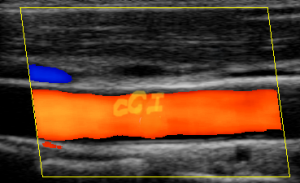

- Ecografía Doppler de vasos cervicales Arteria carotidas (útil para descartar patología vascular).

|